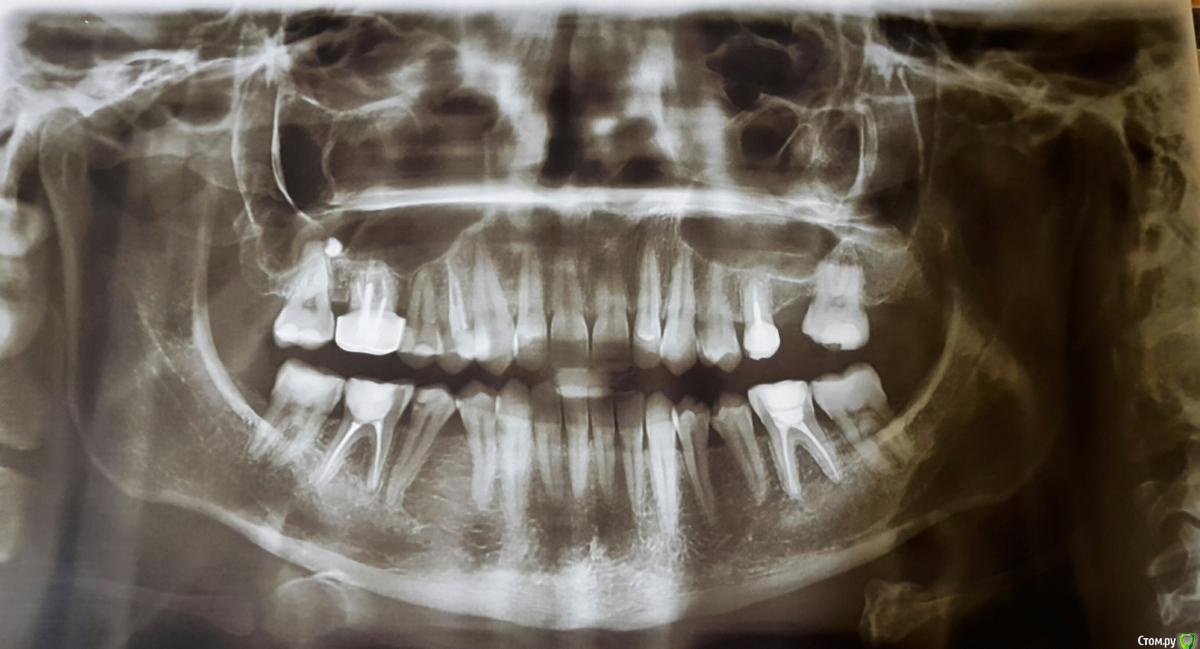

Анастасия Лазарева Опубликовано 15 сентября, 2016 Поделиться Опубликовано 15 сентября, 2016 (изменено) Добрый день, очень прошу совета по своей проблеме. Мне 28 лет. В мае этого года после 2-х часового лечения зубов очень сильно заболела челюсть слева около уха. Чувствую боль также при глотании, иногда отдает в ухо. Больно жевать, особенно жесткую пищу, рот до конца не открывается,максимум на 3-3.5 см. Дальше будто блок. До этого момента в течение многих лет челюсть слева щелкала при зевании и сильном открытии рта, но боли не было, и меня это не беспокоило.Считаю важным отметить, что долгое время я жую все время на правой стороне, тк 6 слева отсутствует с 2005 года. С болью в челюсти обратилась к врачам. Диагноз:двусторонняя болевая мышечно суставная дисфункция внчс..Также отметили неправильный прикус, смещение челюсти, тонус мышц.Предложен план лечения:1. капа. Должна устранить боль в челюсти2. Брекеты для исправления прикуса 3. Имплантация 6 слева.От таких рекомендаций голова кругом... Хотела бы спросить у опытных специалистов прокомментировать мои снимки и фото. Может Вы видите какие-то другие особенности и варианты решения проблемы,которая появилась так внезапно. Заранее очень благодарна за любые рекомендации. Изменено 15 сентября, 2016 пользователем Анастасия Лазарева Ссылка на комментарий

Skip Опубликовано 7 октября, 2016 Поделиться Опубликовано 7 октября, 2016 Хотя он пугает. ..что значит невправляемый? И что посоветуете с этим делать? Там слева гораздо всё серьёзней и похоже на дегенеративный остеоартрит.В этом случае КТ суставов было бы информативней, чем представленные снимки. Ссылка на комментарий